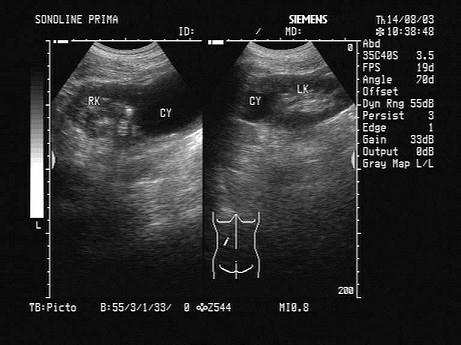

问题 超声检查如图所示,该病例最可能诊断?(?)

选项 A.肾多囊性发育异常 B.肾肿瘤 C.肾囊肿 D.多囊肿 E.肾局限性积水

答案 C